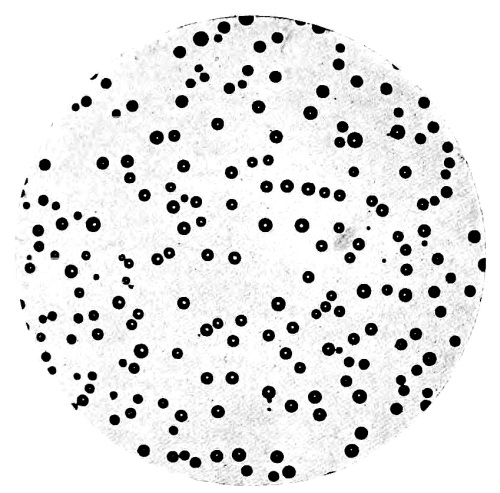

8. Measurement of Blood Corpuscles (human) 97

9. Measurement of Blood Corpuscles (sheep) 97